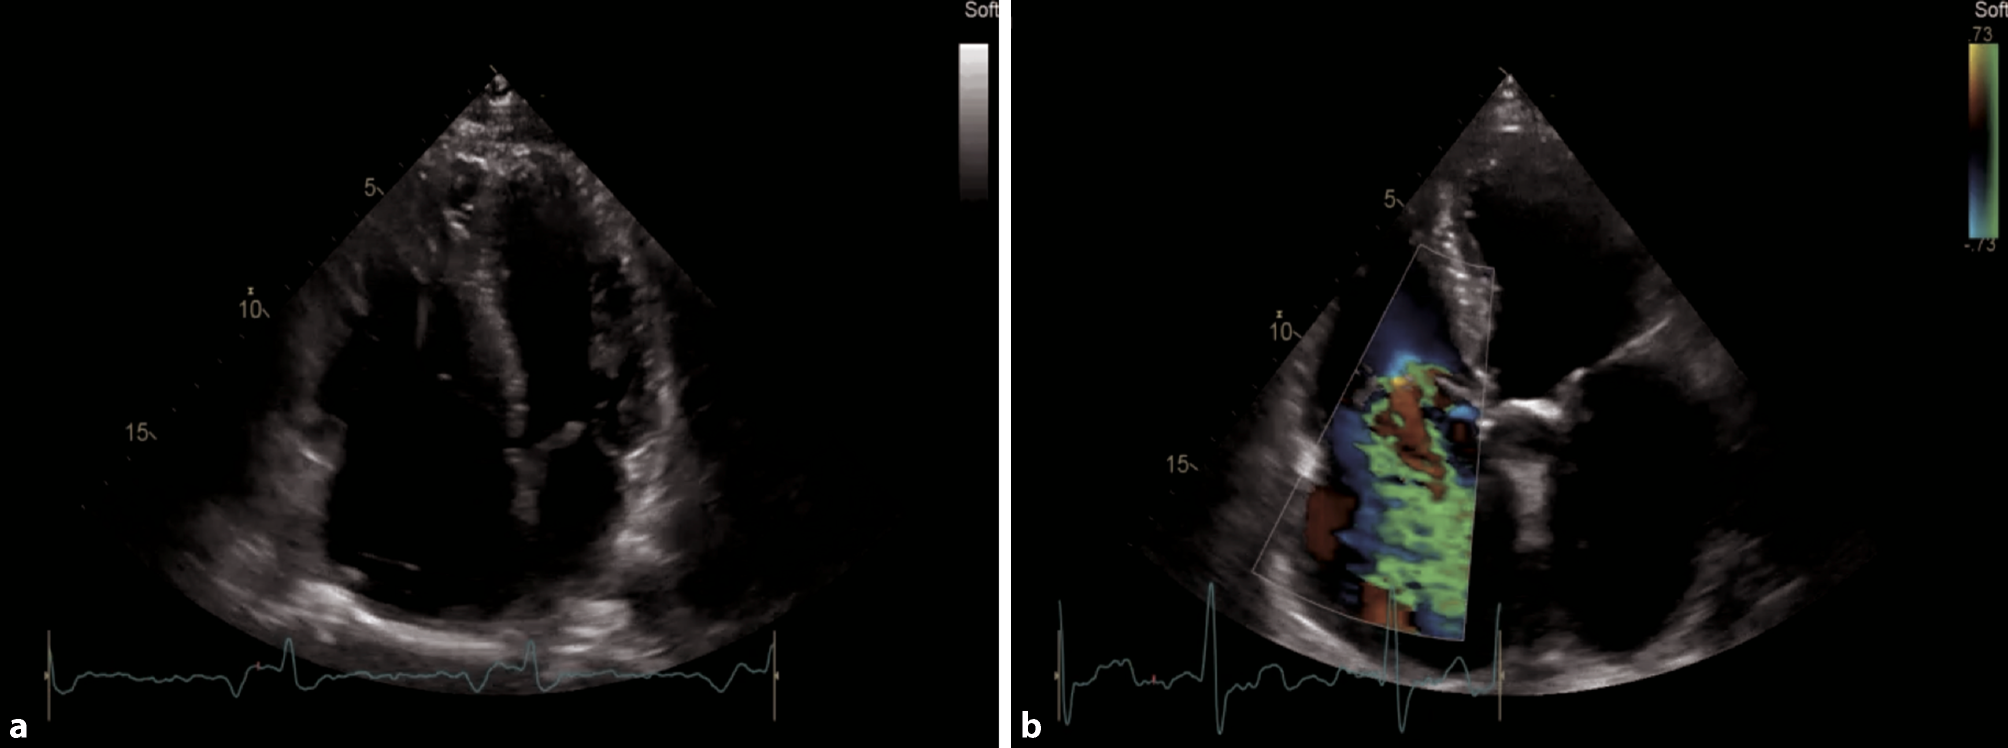

In an acute, hemodynamically relevant pulmonary embolism (PE), the main features in echocardiography are a dilated right ventricle (RV), with the basal diameter >41 mm (as seen in Fig. 15a), reduced RVF, especially at the basal parts, S’ <9.5 cm/s, tricuspid annular plane systolic excursion (TAPSE) <17 mm, sometimes with a hyperdynamic apical region (McConnell sign). The sPAP is normal, low or mildly elevated [52]. A 60/60 sign which describes an sPAP of more than 30 mm Hg but less than 60 mm Hg, and a right ventricular outflow tract acceleration time of less than 60 ms, can be present [53]. The inferior vena cava (IVC) can be dilated with reduced, or even without, respiratory collapsibility. In a parasternal short axis view, a D-shape of the left ventricle can be visualized, and severe tricuspid regurgitation (TR) can be present (Fig. 15b; [54, 55]). None of these echocardiographic findings are specific for acute PE, but in the setting of COVID-19, in particular in an intensive care setting, it is reported that up to one third of patients do develop PE [56].

Fig. 15

Pathologies of the right heart in an apical 4‑ChV. a RV dilatation due to myocarditis. b Severe tricuspid regurgitation

On the ICU, the optimal view to visualize the right heart is a subcostal 4‑ChV, permitting visual assessment of RVF and size. Color Doppler of the region of the tricuspid valve can provide information as to whether severe TR is present (Fig. 15b). Additional views, especially in follow up examinations, include apical and parasternal views, as seen in Figs. 12 and 13. SPAP should be measured with continuous wave Doppler across the tricuspid valve, according to current guidelines [57].